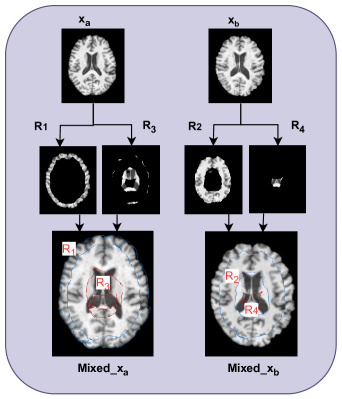

Figure 2: Overview of the mixing strategy. Given two input MRI scans (xax_{a} and xbx_{b}), region-wise masks (R1,R2,R3,R4R_{1},R_{2},R_{3},R_{4}) are extracted to generate mixed samples (Mixed_xa\text{Mixed\_x}_{{}_{a}} and Mixed_xb\text{Mixed\_x}_{{}_{b}}).

After computing the distance transform, two thresholds t1t_{1} and t2t_{2} are set as the minimum and maximum values of the distance transform for each input, ensuring that at least 10% of the brain structure is preserved in each region. This is done to avoid creating excessively small regions. Given a pair of 3D MRIs (xa,xb)(x_{a},x_{b}), the regions are defined as:

where 𝟙()\mathbbm{1}(\cdot) represents an indicator function that returns 1 if the condition inside is true and 0 otherwise. The variables R1,R2,R3,R_{1},R_{2},R_{3}, and R4R_{4} are mutually exclusive binary masks, each defining different spatial regions within the image. The terms DaD_{a} and DbD_{b} correspond to the distance transforms of the images xax_{a} and xbx_{b}, respectively. These thresholds divide the MRI into four non-overlapping regions (Fig. 2). The mixed image is constructed as: